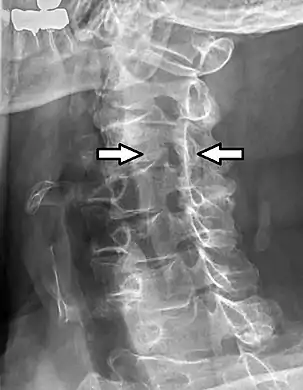

Cervical spinal nerve 4

Projectional radiograph of a man presenting with pain by the nape and left shoulder, showing a stenosis in the intervertebral foramen of cervical spinal nerve 4, corresponding with the affected dermatome.